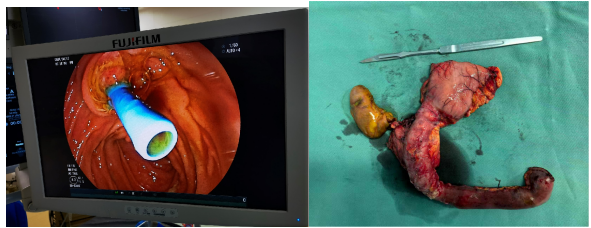

、腹腔镜、胆道镜、十二指肠镜多镜联合复合手术

我科的特色诊疗技术之一,即利用腹腔镜、胆道镜、十二指肠镜的多种微创内镜技术,联合各种内镜的优势治疗复杂肝内外胆管结石、胆囊结石,能够保持胆管完整性、不需要放置T管引流的优势,将两次手术减少为一次性微创手术,将两次麻醉减少为一次麻醉,使肝胆外科医生能够克服传统手术盲取结石的"取之不尽、并发症多"的弊端,避免留置胆道 T 管给患者带来的痛苦和不便,使胆系结石等疾病的治疗达到微创化、可视化、精准化,减轻了病人的痛苦,提高了治疗效果。是广大受结石困扰患者的福音。